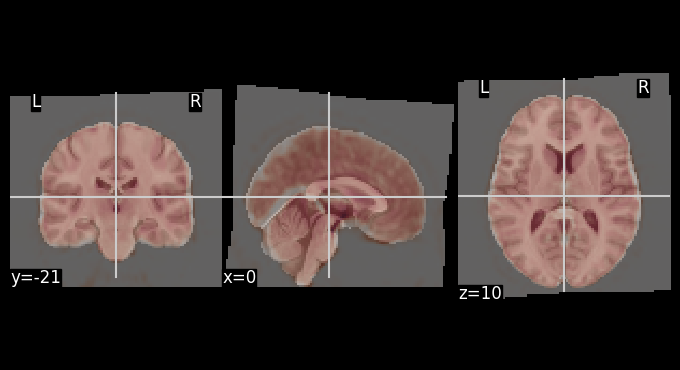

The mean BOLD image after motion correction was registered to the MNI template. The overlays below allows for visual inspection of alignment quality.

# Get mean BOLD image

mean_bold = image.mean_img(result_parallel.bold_preproc[0], copy_header=True)

# Overlay of the mean bold image on MNI background template

plotting.plot_stat_map(stat_map_img=mean_bold,

bg_img=template,

transparency=0.4,

colorbar=False)

<nilearn.plotting.displays._slicers.OrthoSlicer at 0x7f2fe916e510>